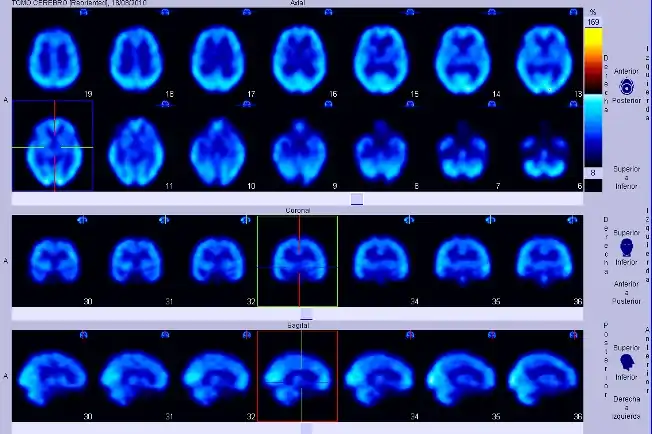

Las imágenes digitales que se adquieren hoy en día, ya sea en radiología digital indirecta (CR) o directa (DR), presentan una gran ventaja debido a la potencialidad que su manejo informático ofrece, en el cual es posible sobre la base de una imagen adquirida aplicar diferentes herramientas como filtros que permiten mejorar el realce de los bordes, suavizar, analizar el histograma y realizar análisis de la calidad de la imagen obtenida. Estas herramientas están disponibles en las consolas de procesado de imágenes de los equipos radiológicos, pero también existen programas dedicados como ImageJ que permiten realizar el análisis de las imágenes, ya sean de uso médico o no. Una de las funcionalidades de ImageJ es la posibilidad de "retocar" la imagen aplicando filtros como los que se observan en las siguientes imágenes en las cuales hemos aplicado a la imagen base de una radiografía de cráneo (al centro) un filtro que permite suavizar la imagen (Imagen 1) y luego a la misma imagen le hemos aplicado un filtro de reforzamiento de los bordes (Imagen 2).

-

Imagen 1 -

Imagen 2 -

Imagen basal